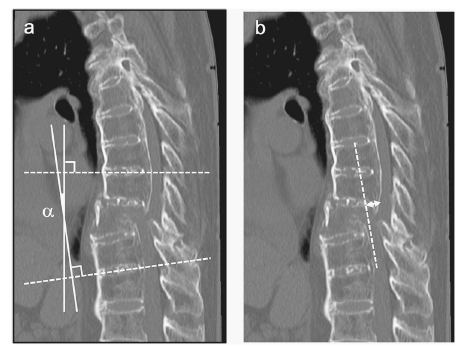

Diffuse idiopathic skeletal hyperostosis (DISH) frequently occurs in the spine, resulting in unstable fractures. Treating thoracolumbar fractures in patients with DISH is often difficult because the anterior opening of the vertebral body is exacerbated by dislocation in the prone position, making reduction difficult. In this study, we introduced a novel skull clamp-assisted positioning (SAP) technique. The patient is placed in a supine position with a skull clamp used in cervical spine surgery before surgery to prevent the progression of dislocation and to restore the patient's position. Using this method, the mean difference in local kyphosis angle improved from -2.9 (±8.4)° preoperatively to 10.9 (±7.7)° postoperatively. Furthermore, posterior displacement decreased from a preoperative mean of 5.5 (±4.3) mm to 0.3 (±0.7) mm postoperatively. Complications such as neurological sequelae, implant fracture, and surgical site infection were not observed through one year of postoperative follow-up. SAP may decrease invasiveness and complications. Longer-term studies and larger sample sizes are needed to establish long-term efficacy and benefits.